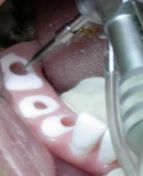

Fasi chirurgiche implantari dell’emiarcata destra con ausilio della dima:

Si è utilizzato un micromotore a contrangolo, con riduttore , impostando i Gpm. a bassissima velocità a 38 giri/min senza irrigazione per non surriscaldare l’osso.

La sequenza di perforazione è stata effettuata in zona del 4.6, 4.4, 4.3 3.6.3.4 e 3.3 con una fresa a lancia di per praticare il foro d’invito sulla corticale, seguita dalla sequenza di frese calibrate a diametro crescente per la preparazione atraumatica, e dotate di tacche di riferimento per l’altezza prescelta; tra cui la fresa pilota per raggiungere la lunghezza di lavoro, seguendo la perforazione dei siti implantari con frese a spirale ø 2,00 - 2,5 – mm., tenendo presente l’asse d’inserzione implantare, che deve tenere in considerazione l’inclinazione della radice cresta edentula; per il parallelismo utilizziamo dei pin di riferimento.

L’utilizzo di un profondimetro ha permesso la verifica del sito ottenuto.

Figura 23 – 24 – 25 inserimento del I° minimpianto in zona 4.6

Figura 26 – 27 – 27 inserimento del II° minimpianto in zona 4.4

Figura 28 – 29 – 30 inserimento del III° minimpianto in zona 4.3